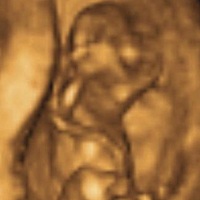

11周的nt 有会看的宝妈吗